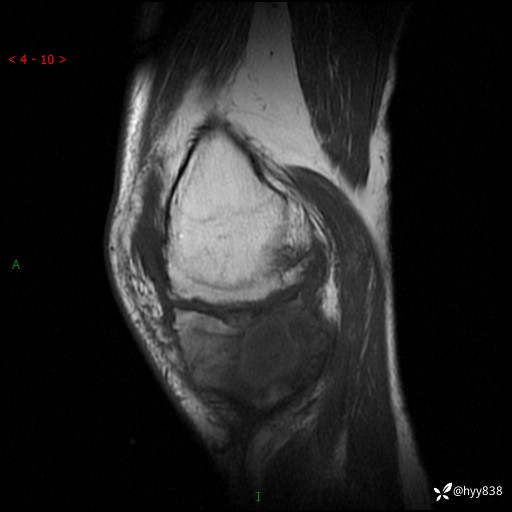

MRI(sag :T1WI+T2WIfs)